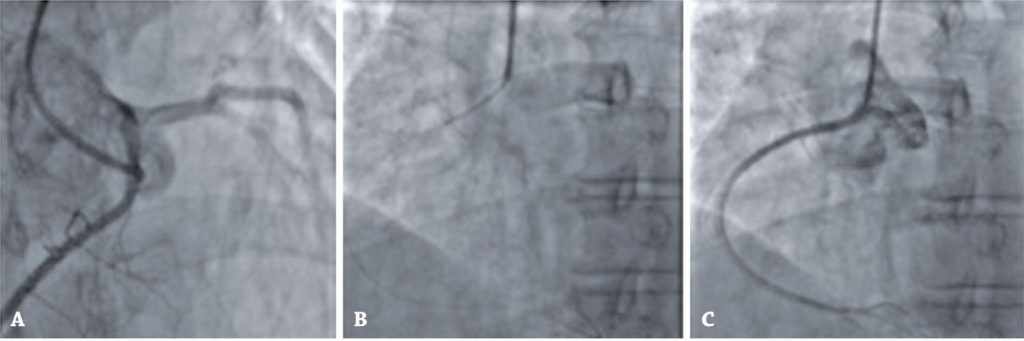

Figure 10

Coronary angiography images illustrating case 3. (A) Right coronary artery originating from the left coronary sinus. (B) Drug-eluting stent implantation in the proximal portion of the right coronary artery. (C) Post-treatment angiographic result.